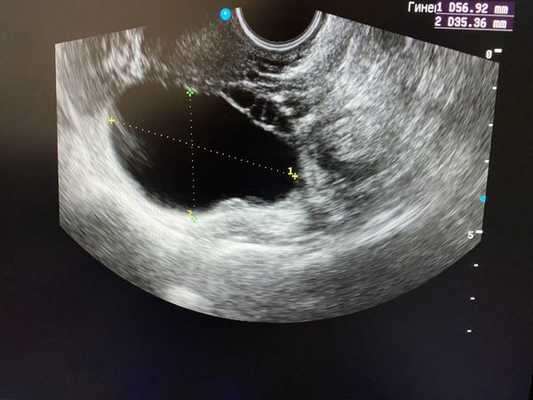

- Ультразвуковое исследование, которое позволяет увидеть в пораженном яичнике большое желтое тело с признаками кровоизлияния в него и/или свободную жидкость (кровь) в животе.

Ультразвуковое исследование органов малого таза является наиболее простым и высокоинформативным методом диагностики различных кист яичников.

Безусловно, проведение ультразвуковой диагностики трансабдоминальным и трансвагинальным датчиками позволит не только выявить локализацию кисты, но и определить ее структуру, размеры, характер жидкостного содержимого, определить тактику лечения пациентки. Особенностью фолликулярных кист при ультразвуковом исследовании является тонкостенная капсула с отсутствием сосочков внутренней стороны капсулы. [10] Диагностировать кистозные образования у беременных женщин значительно труднее, ввиду увеличения размеров матки на соответствующих сроках беременности, поэтому ультразвуковое исследование стоит проводить с ЦДК и доплерометрией [11] .

- УЗИ малого таза. Ультразвуковая картина при апоплексии яичника характеризуется наличием свободной жидкости в животе, признаками кровоизлияния в овариальную ткань на пораженной стороне.